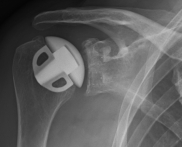

Surface replacement ("cap prosthesis" of the humeral head) in cases of mild omarthrosis and still well-preserved glenoid cavity

links: X-ray image of a cap prosthesis ("surface replacement")

right: cap prosthesis ("surface replacement", type "Durom" Fa. Zimmer)gkl